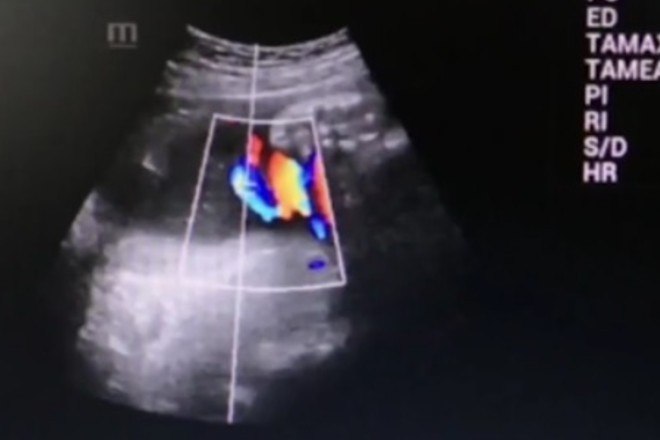

Um bebê chinês sobreviveu e nasceu com o cordão umbilical enrolado seis vezes em torno do pescoço

A equipe responsável pelo parto informou que o cordão umbilical media aproximadamente 90 cm de comprimento, cerca de 40 cm a mais do que a média habitual

Li Hua, supervisora do Departamento de Obstetrícia do hospital, explica que esse tamanho superior foi o que possibilitou o nascimento da criança, sem que ela enfrentasse nenhum risco de estrangulamento durante o parto

Os médicos descobriram a condição do bebê durante uma verificação pré-natal, duas semanas antes nascimento. No entanto, eles decidiram não tomar nenhuma medida, já que a mãe e a criança estavam saudáveis